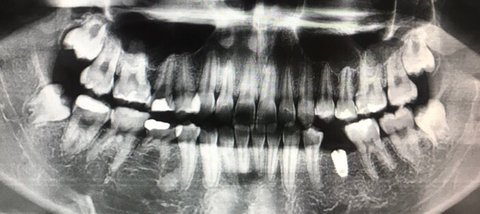

얘들아 나 사랑니 4개 다 있음

그중 1개는 지금 점점 모습 드러내는중임

나도 근데 난 누웠다 ㅠ